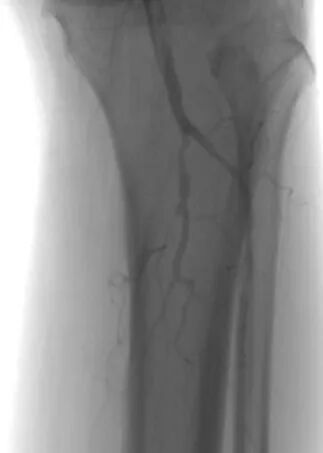

另一个病例中,患者病情更为复杂。术前CTA检查显示,其股浅动脉至腘动脉全程闭塞,血管外科将这种情形称为“长段无光区”。传统治疗中,开通此类如同“水泥管”般的长段闭塞血管,难度极大,术者如同在黑暗中摸索,导丝极易误入内膜下形成夹层,导致手术失败。

2.png

术中,血管外科团队以IVUS为“导航”,在其实时监视下,导丝精准找到血管真腔入口,顺利通过全程闭塞段,成功避免夹层发生,顺利打通患者腿部“生命通道”。针对血管开通后管腔内的严重增生性病变,团队采用准分子激光消融术进行减容处理,通过激光导管冷光源精准气化斑块,进一步恢复了血管正常内径。